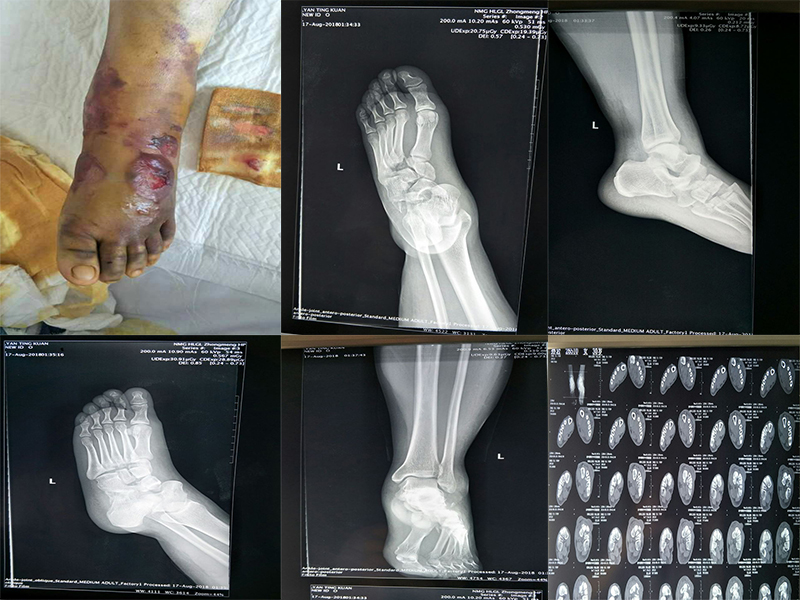

toe-up sign 12 ~ 24 h 7 ~ 10 Lisfranc Hardcastle A 1 5 1 2 3 4 AO 3.5mm 4.0mm 3.5mm 1 2 Ⅰ 8 ~ 12 4 . 5 6 ~ 8 3 ~ 4

Lisfranc 2mmm